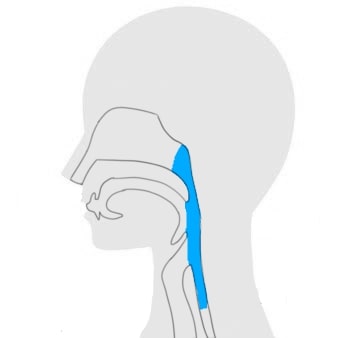

この治療法は、特定の薬剤と光を組み合わせてがん細胞を破壊するもので、口腔がんの治療にも適応できる可能性があります。

光免疫療法は、特定の波長の光を利用して、薬剤を活性化させることでがん細胞を攻撃します。

その後、特定の波長の光を当てることで、薬剤が活性化し、がん細胞を破壊することができます。